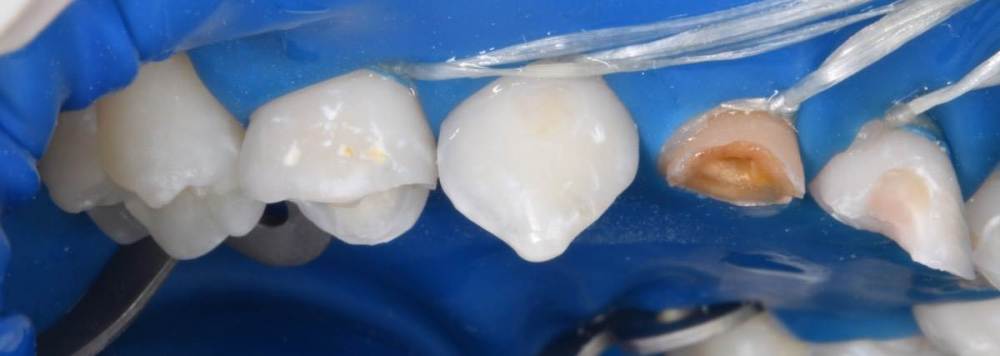

CRAZYDUCK Опубликовано 30 июня, 2022 Автор Поделиться Опубликовано 30 июня, 2022 Пример лечения обратимого пульпита 7.5 зуба . 2 1 Ссылка на комментарий